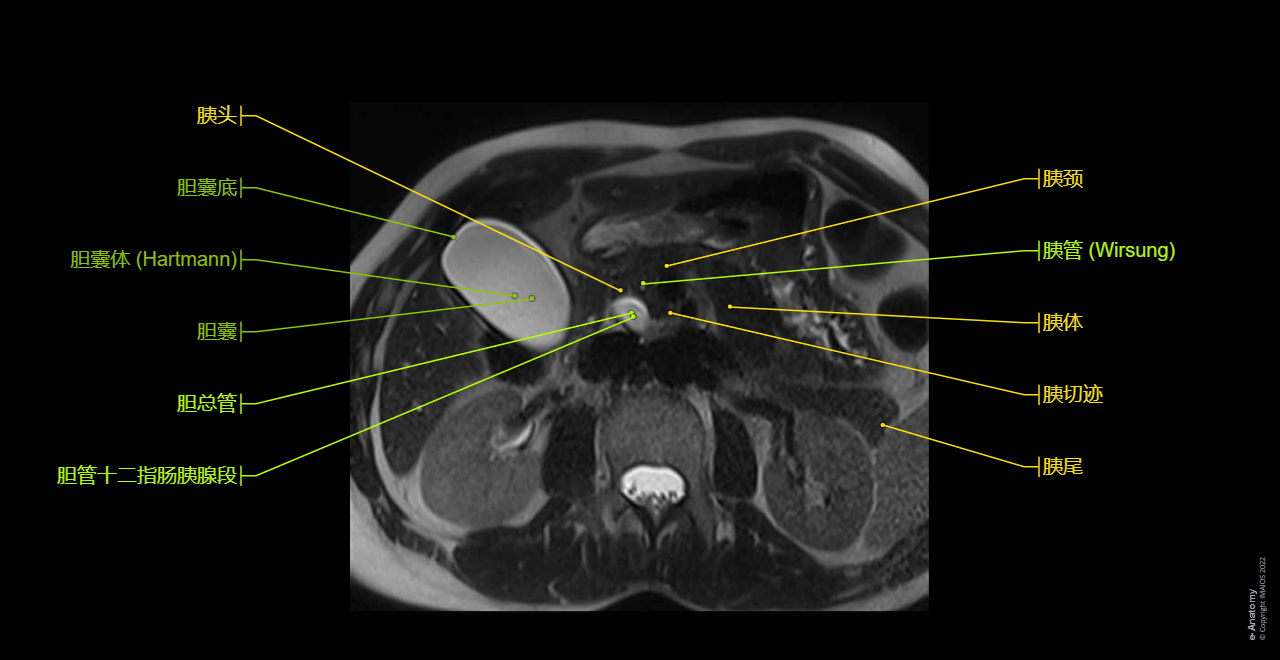

This anatomical module of e-Anatomy is dedicated to the anatomy of the biliary tract on MRI on a MRCP (magnetic resonance cholangiopancreatography).

To emphasize our pedagogic goal in anatomy, we did not choose a healthy patient where the thin (not dilated) biliary tree may have been difficult to see on MRI, but a patient with dilated biliary tree (intrahepatic ducts and common bile duct) on a choledocholithiasis (gallstone) of the distal common bile duct.

Axial T2 HASTE: Axial breath-hold T2-weighted turbo spin-echo (TSE), 5 mm slices, on the whole biliary tract. Two breath-hold acquisitions are obtained so that the whole of the liver down to the duodenal ampulla is visualized.

Axial T1 in-phase and axial T1 out-of-phase on the liver: Conventional abdominal MRI imaging to study extraductal structures (hepatic segments, pancreas, spleen, kidneys)